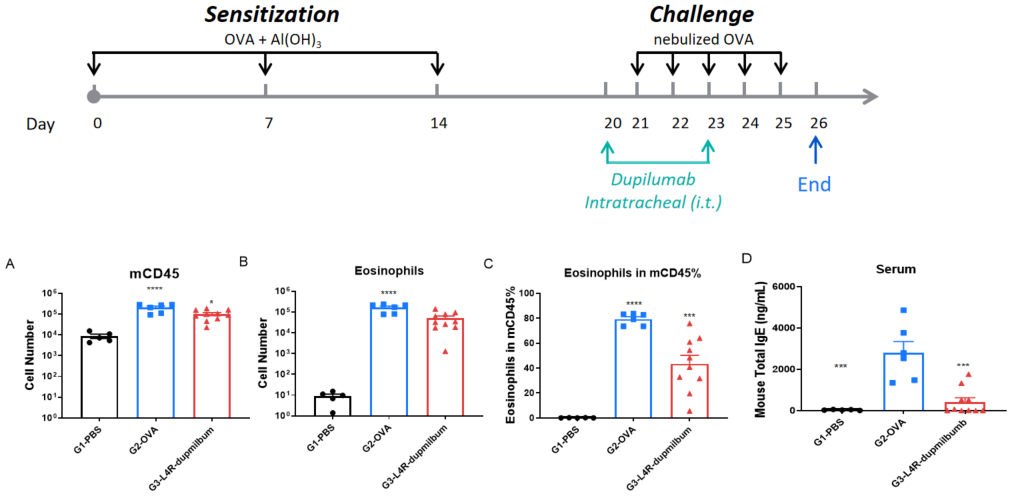

B-hIL4/hIL4RA mice were sensitized and challenged with OVA by intratracheal (i.t.) administration to induce asthma. Dupilumab was administered intratracheally. Panels show total leukocytes (A), eosinophils (B), eosinophil percentage in CD45⁺ cells (C), and serum total IgE (D). Dupilumab significantly reduced airway inflammation and IgE levels.